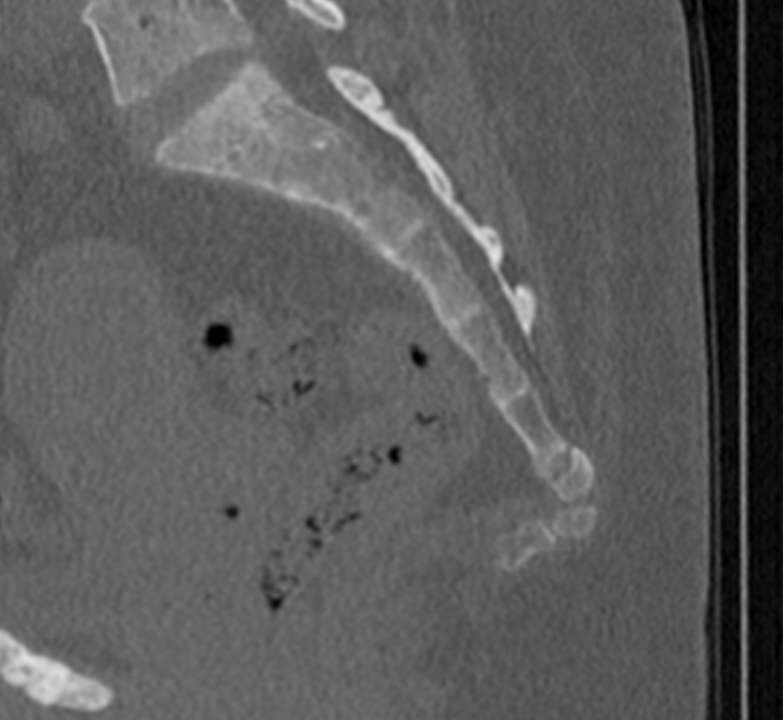

Одним из наиболее информативных методов диагностики заболеваний копчика является мультиспиральная компьютерная томография. Метод основан на использовании рентгеновского излучения и применения инновационных компьютерных программ для детальной визуализации состояния органов и систем организма. Процедура отличается быстротой, безболезненностью и неинвазивностью (то есть проводится без нарушения целостности кожи и расположенных под ней тканей).

Инновационные возможности аппаратов дают возможность получить множество послойных снимков высокого качества и реконструировать на их основе трехмерную модель органа. Кроме того, аппаратура позволяет за счет сокращения времени сканирования максимально уменьшить лучевую нагрузку на пациента.

Что покажет КТ копчика

- перелом крестца или копчика, смещение позвонков и другие травмы, в том числе застарелые.